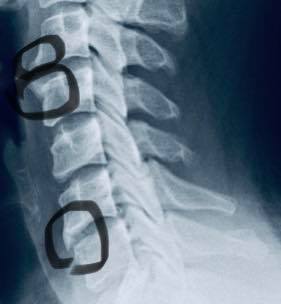

😂😂林先生在十年前出一場嚴重車禍導致胸椎跟頸椎受傷,X光片顯示頸椎前緣骨質增生、第二第三關節突增生、第六第七關節突卡壓 ,胸椎歪斜,最困擾症狀是上背悶痛,這幾年幾乎每周都會安排推拿,可以緩解胸悶的情況,但是一直沒有重大改善,狀況不好的時候也會引發背痛 ,來診前的這幾個月幾乎是每天都會痛,經過友人介紹來接受脊椎整合中醫微創療法

✳️診斷:胸椎小關節面沾黏合併頸椎神經根卡壓